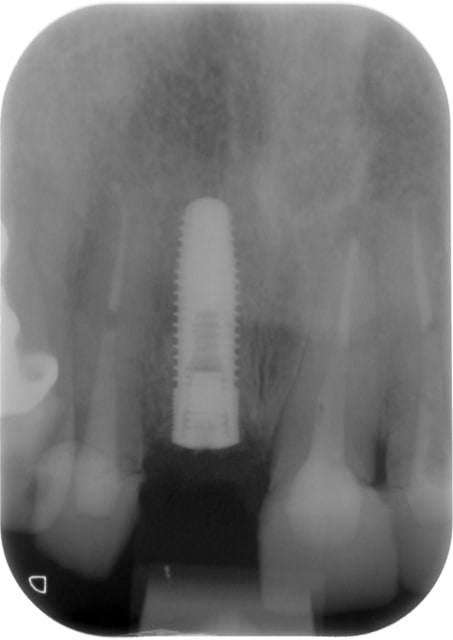

14/03/2011 à 10h43

la radio post op

carototo